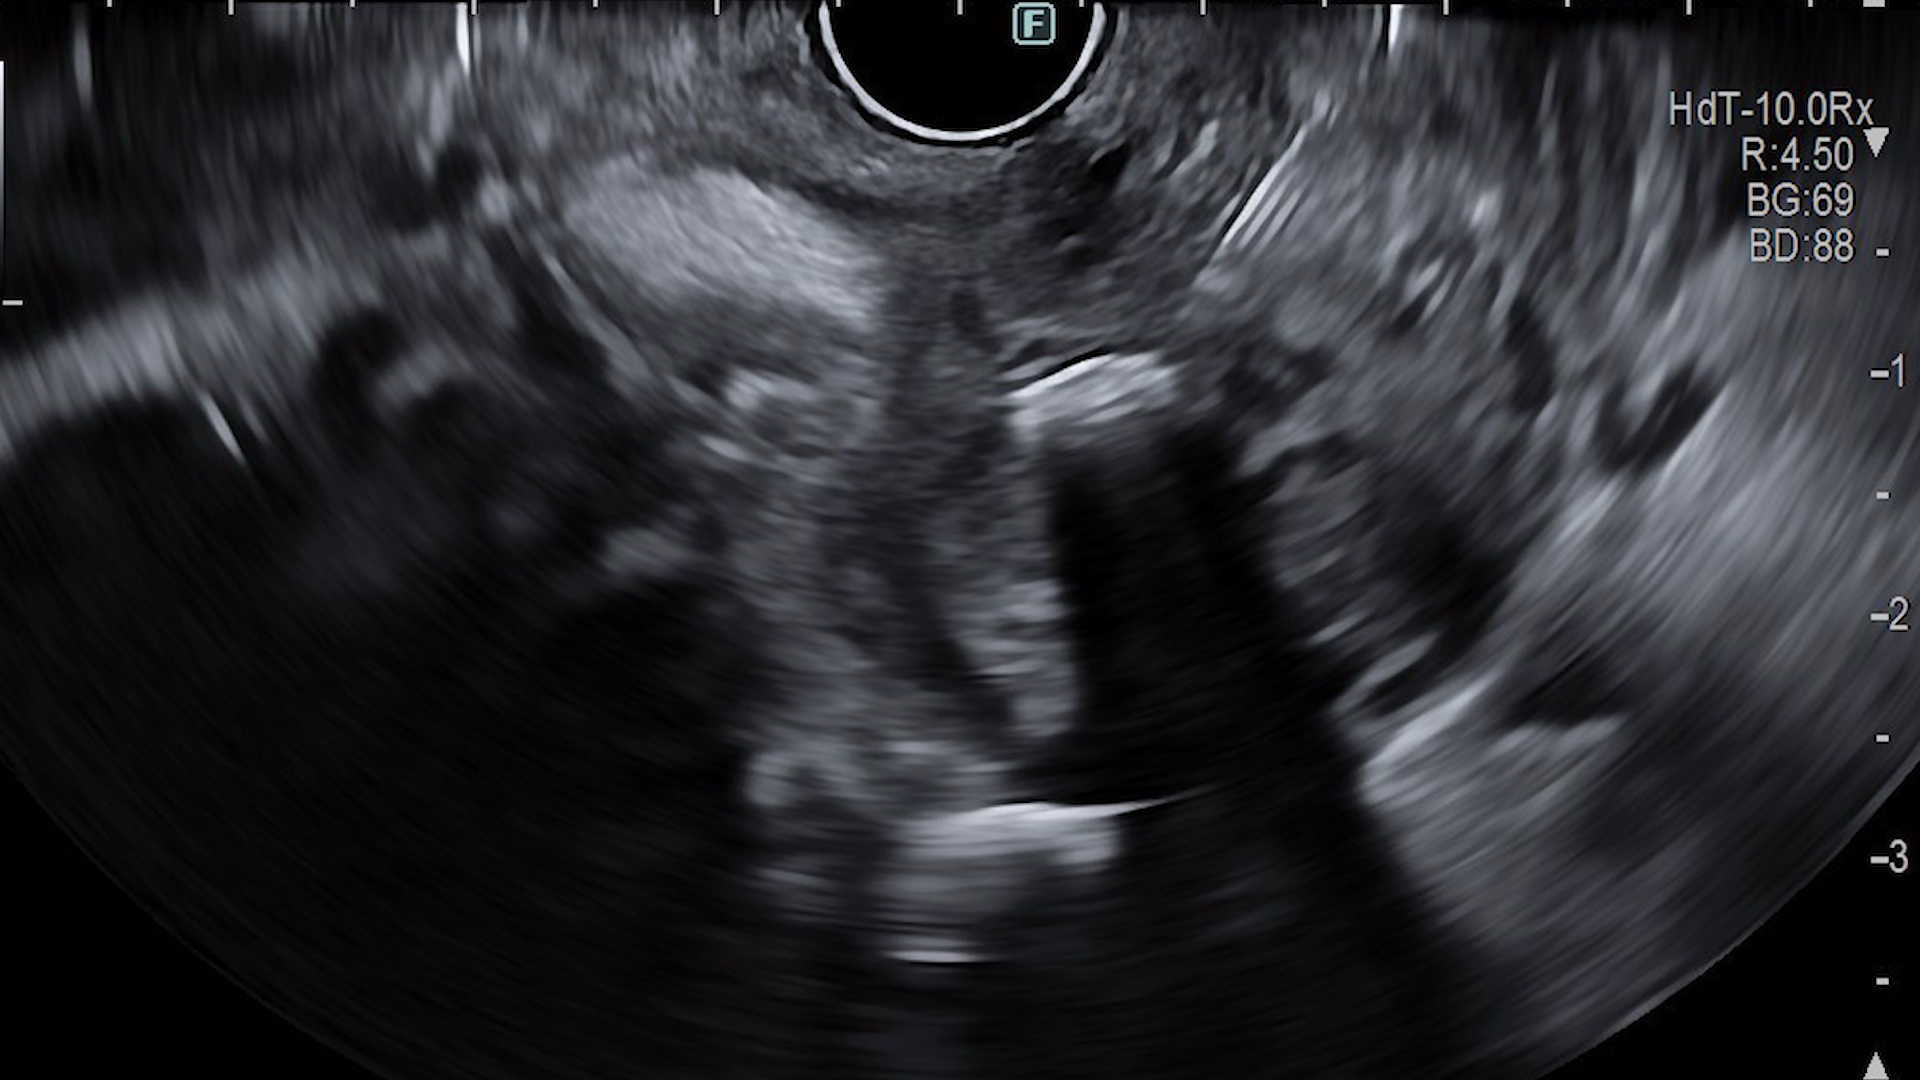

Ecoendoscopic (EUS) s-a evidențiat:

- Evaluarea ecoendoscopică:

- Modificări infiltrative ale parenchimului pancreatic cu extensie parietală gastrică și bulbară;

- Parenchim pancreatic global atrofic;

- Duct pancreatic principal dilatat difuz, cu traiect tortuos, conținând material ecogen sugestiv pentru mucină, precum și imagini hiperecogene cu con acustic posterior mobilizabile cu vârful acului de puncție, sugestive pentru mucină calcificată;

- Dilatarea ductelor pancreatice secundare.

- Ecoendoscopie cu substanță de contrast (CE-EUS):

După administrarea intravenoasă a 4,8 mL SonoVue, se identifică la nivel cefalopancreatic o zonă hipocaptantă, imprecis delimitată, cu ecostructură neomogenă, cu dimensiuni de aproximativ 40/26 mm. Leziunea a fost puncționată ecoendoscopic (EUS-FNB), efectuându-se două pasaje cu ac de 22G (Acquire, Boston Scientific).